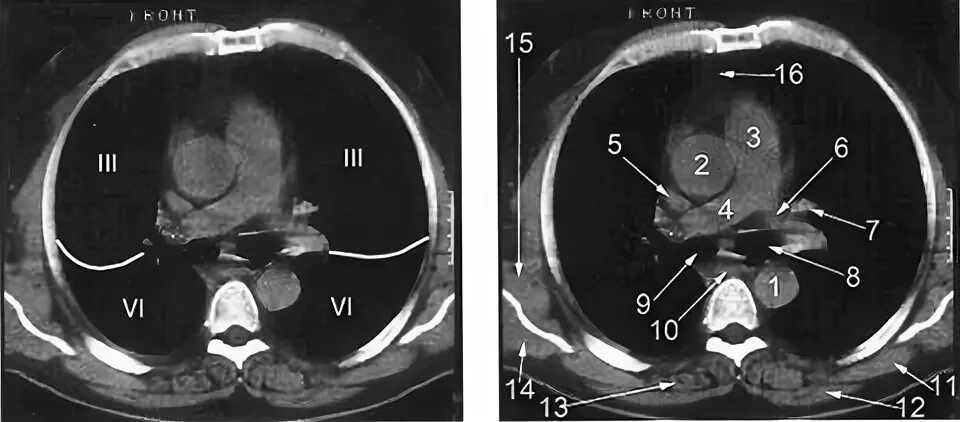

Легочный ствол на кт